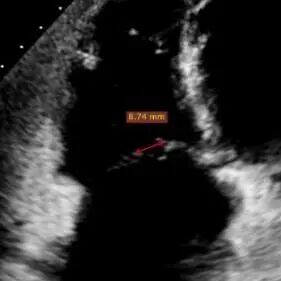

After induction of general anesthesia, the jugular vein was punctured for vascular access, with one Proglide pre-deployed. An 18Fr delivery sheath was advanced over a stiff guidewire to the mid-right atrium. Under echocardiographic guidance, the delivery system was introduced. A 14T K-Clip® and a 16T K-Clip® were deployed at the posterior annulus and anteroposterior annulus, respectively.The angle between the device and the annular plane was adjusted by steering and rotation to direct the device tip toward the target. The anchoring component was implanted at the annulus under echocardiographic MPR guidance. After stable traction, the clamping arms were opened and apposed to the annulus. The anchoring component was then retracted to close the clamping arms and achieve annular plication. Intraoperative assessment demonstrated satisfactory procedural results. The delivery system was disconnected and removed.

The anchoring component was deployed under the MPR view

Determine the screw driving point at the Hinge under MPR